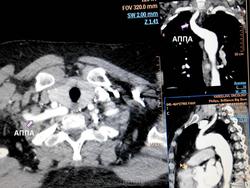

Автор: Бодров Юрий Дмитриевич . Аберрантная правая подключичная артерия